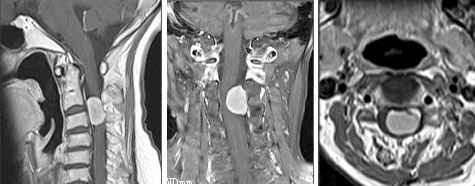

病例3  颈2齿状突陈旧性骨折并寰椎脱位,后路寰枢椎椎弓根螺钉复位固定融合术。

患者56岁,男性,颈2齿状突陈旧性骨折并寰椎脱位。

患者颈部外伤后2年入院,四肢肌力、感觉正常。

术后寰枢椎即可复位,术后患者四肢肌力、感觉正常。

术中使用电钻寰椎置钉道